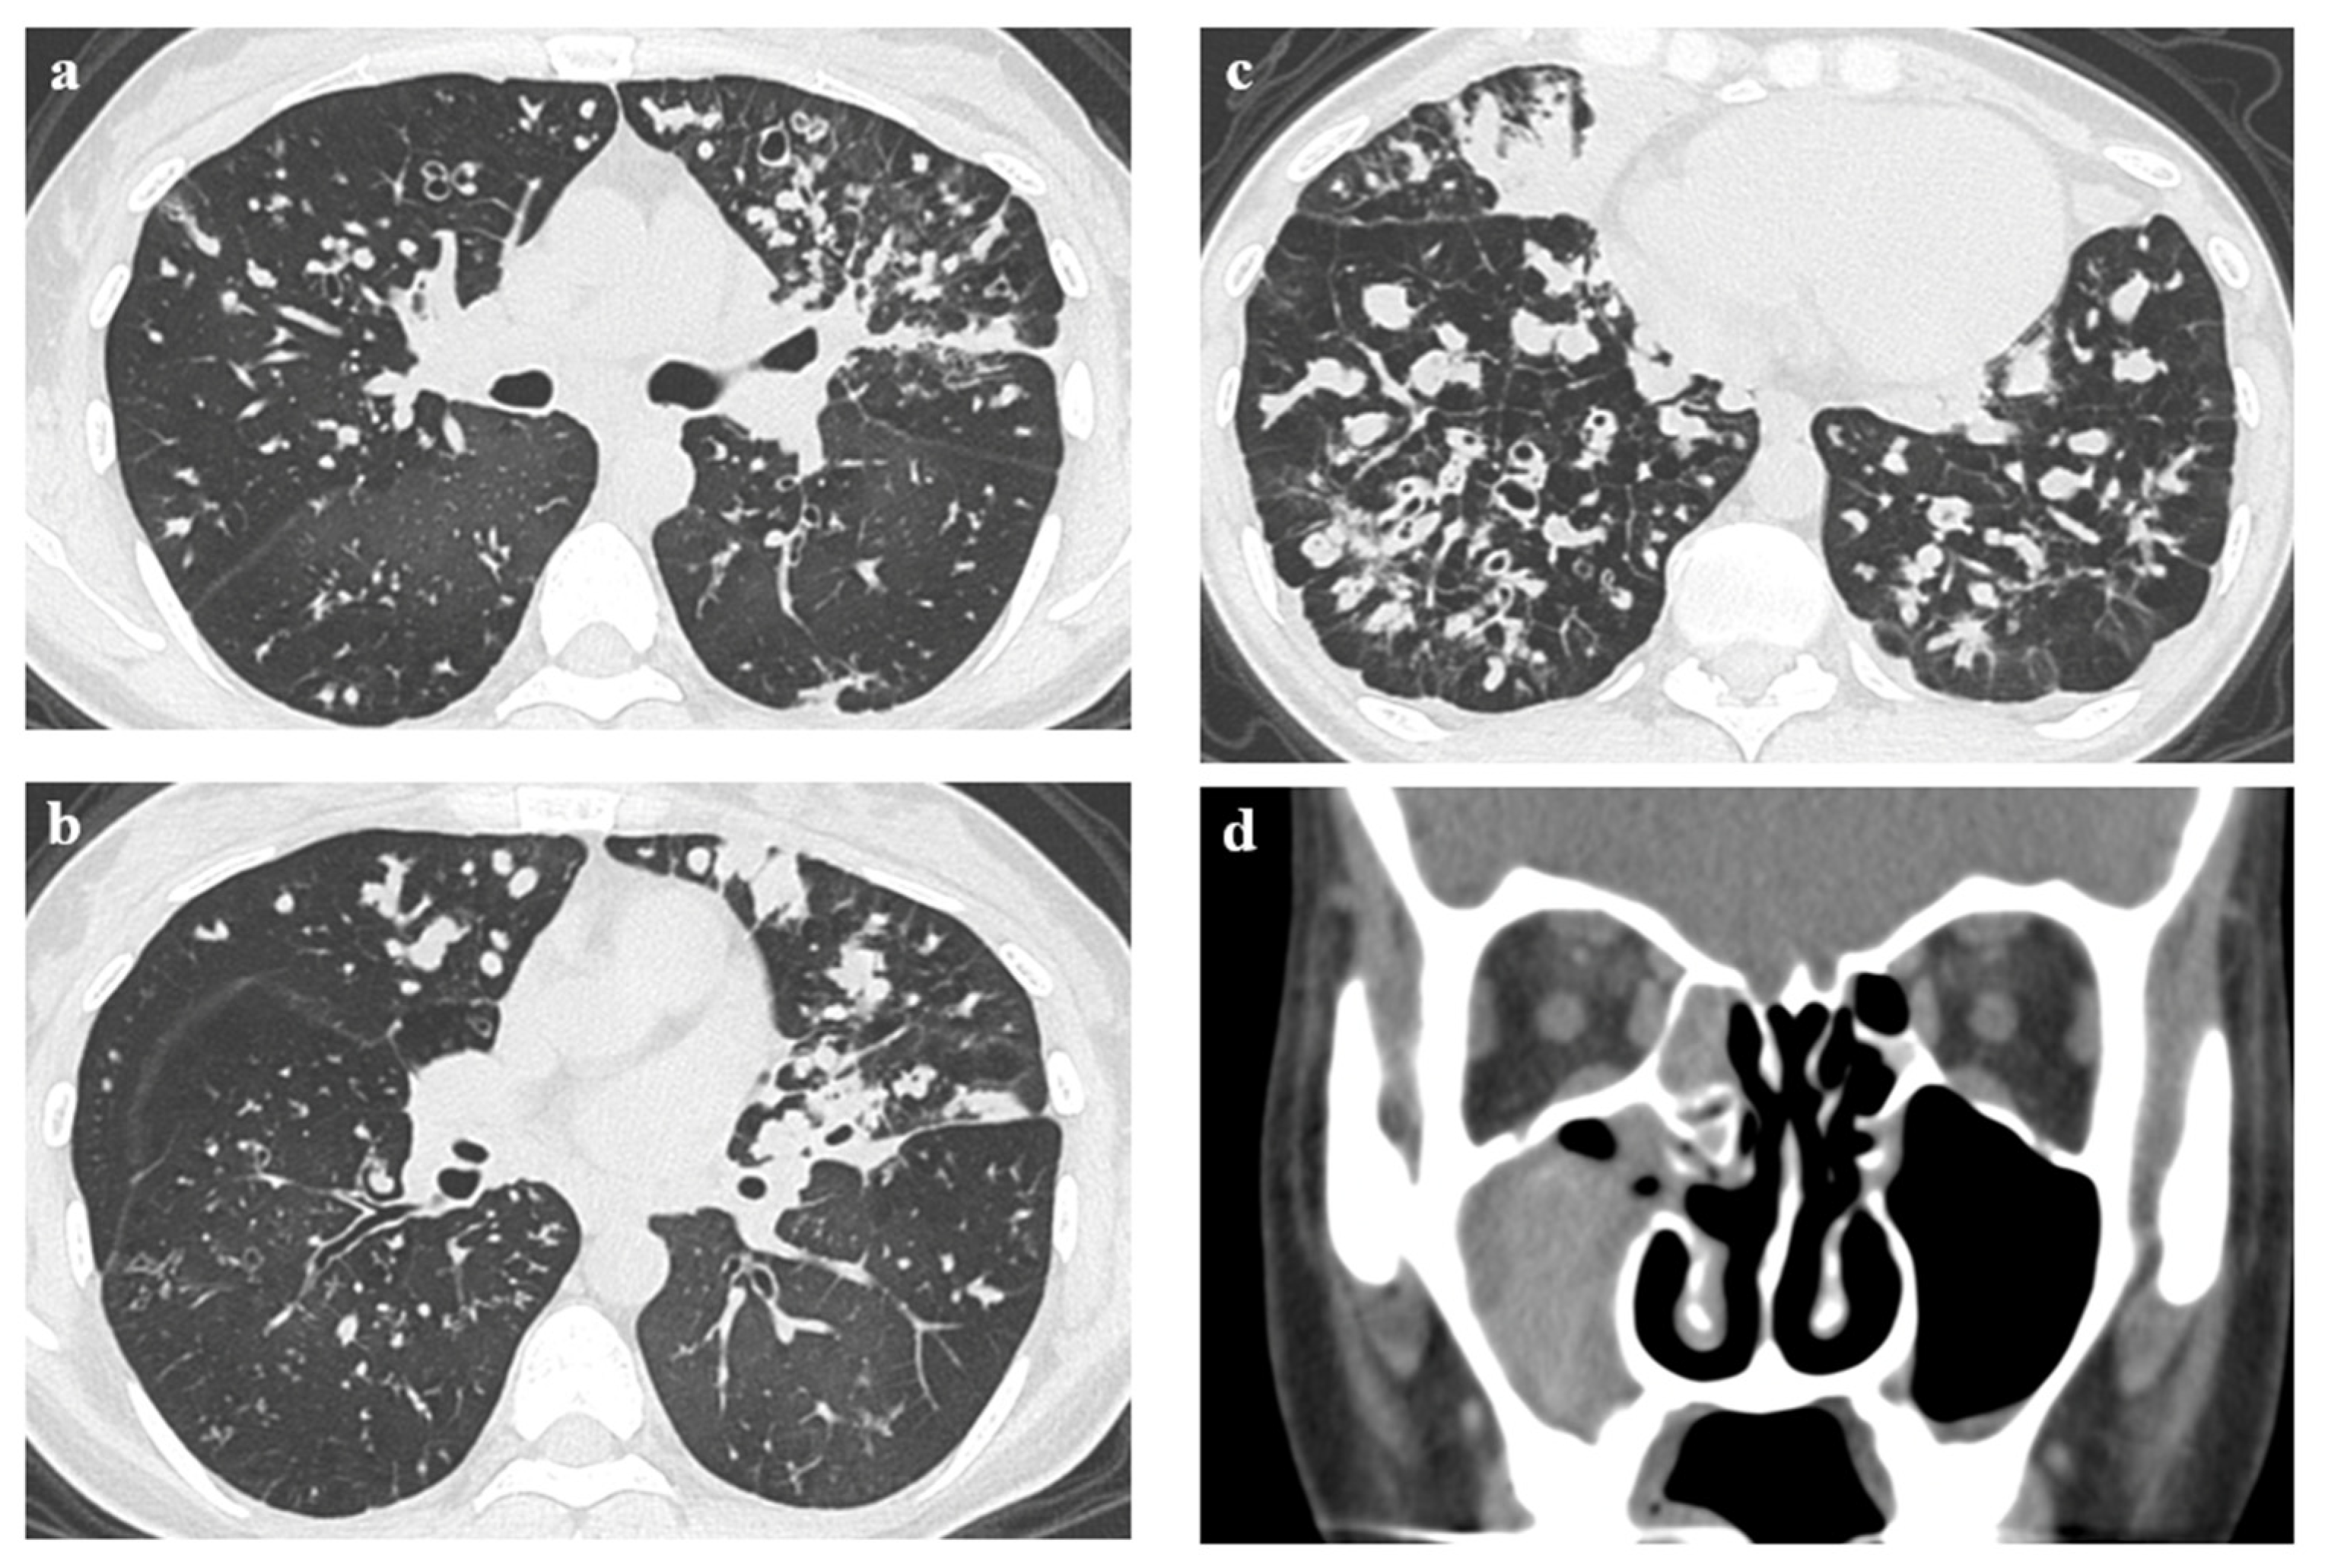

2. Case Presentation